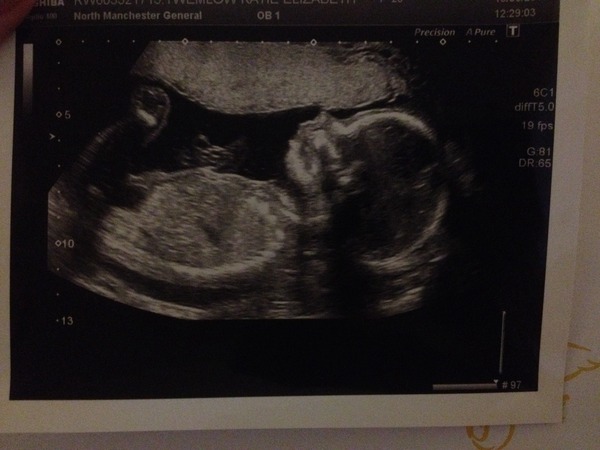

Forgot to post the pic!

Here's our little boy, once he decided to keep still - ooo it feels weird being able to say he!